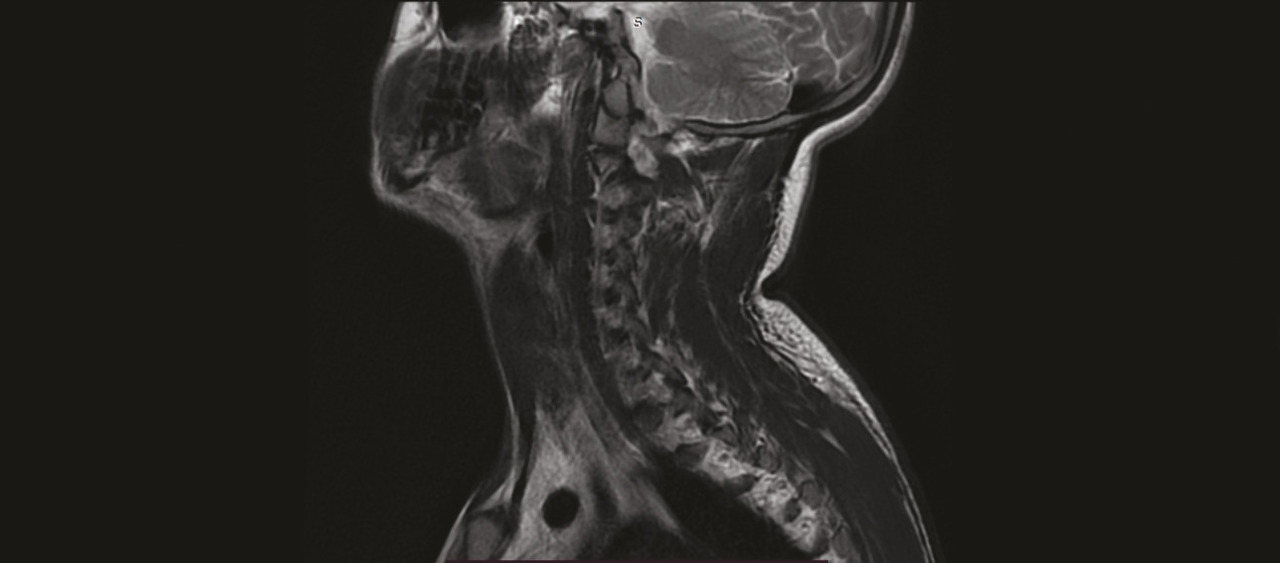

Un homme de 21 ans est admis en service de réanimation pour convulsion fébrile, quelques semaines après avoir été rapatrié d’une mission en zone d’endémie palustre pour des crises convulsives. Le diagnostic d’un accès palustre à Plasmodium falciparum est confirmé. L’évolution est marquée par la survenue d’un déficit moteur et sensitif au niveau des deux membres supérieurs avec une amyotrophie des muscles de la ceinture scapulaire ; un syndrome de Parsonage-Turner post-infectieux est suspecté (fig. 1 ). Un électromyogramme, une imagerie par résonance magnétique (IRM) du plexus brachial (fig. 2 ) et un scanner des épaules sont en faveur d’une luxation antérieure post-convulsive des deux épaules (fig. 3 et 4 ).

Les luxations antérieures invétérées de l’épaule sont extrêmement rares. Elles sont définies par une luxation non réduite après la troisième semaine ; elles posent toujours un problème diagnostique et thérapeutique. La cause est majoritairement traumatique, parfois post-convulsive, et peut être aussi la conséquence d’une immobilisation non surveillée après réduction d’une luxation antérieure.1 Le diagnostic est difficile, car la douleur initiale diminue rapidement sans disparaître. La limitation des amplitudes articulaires passe alors au premier plan : la mobilité globale est limitée en abduction et en rotation interne.

Les radiographies standard contribuent à poser le diagnostic ; le scanner permet d’appréhender le siège exact et l’étendue des lésions osseuses de passage antérieur.